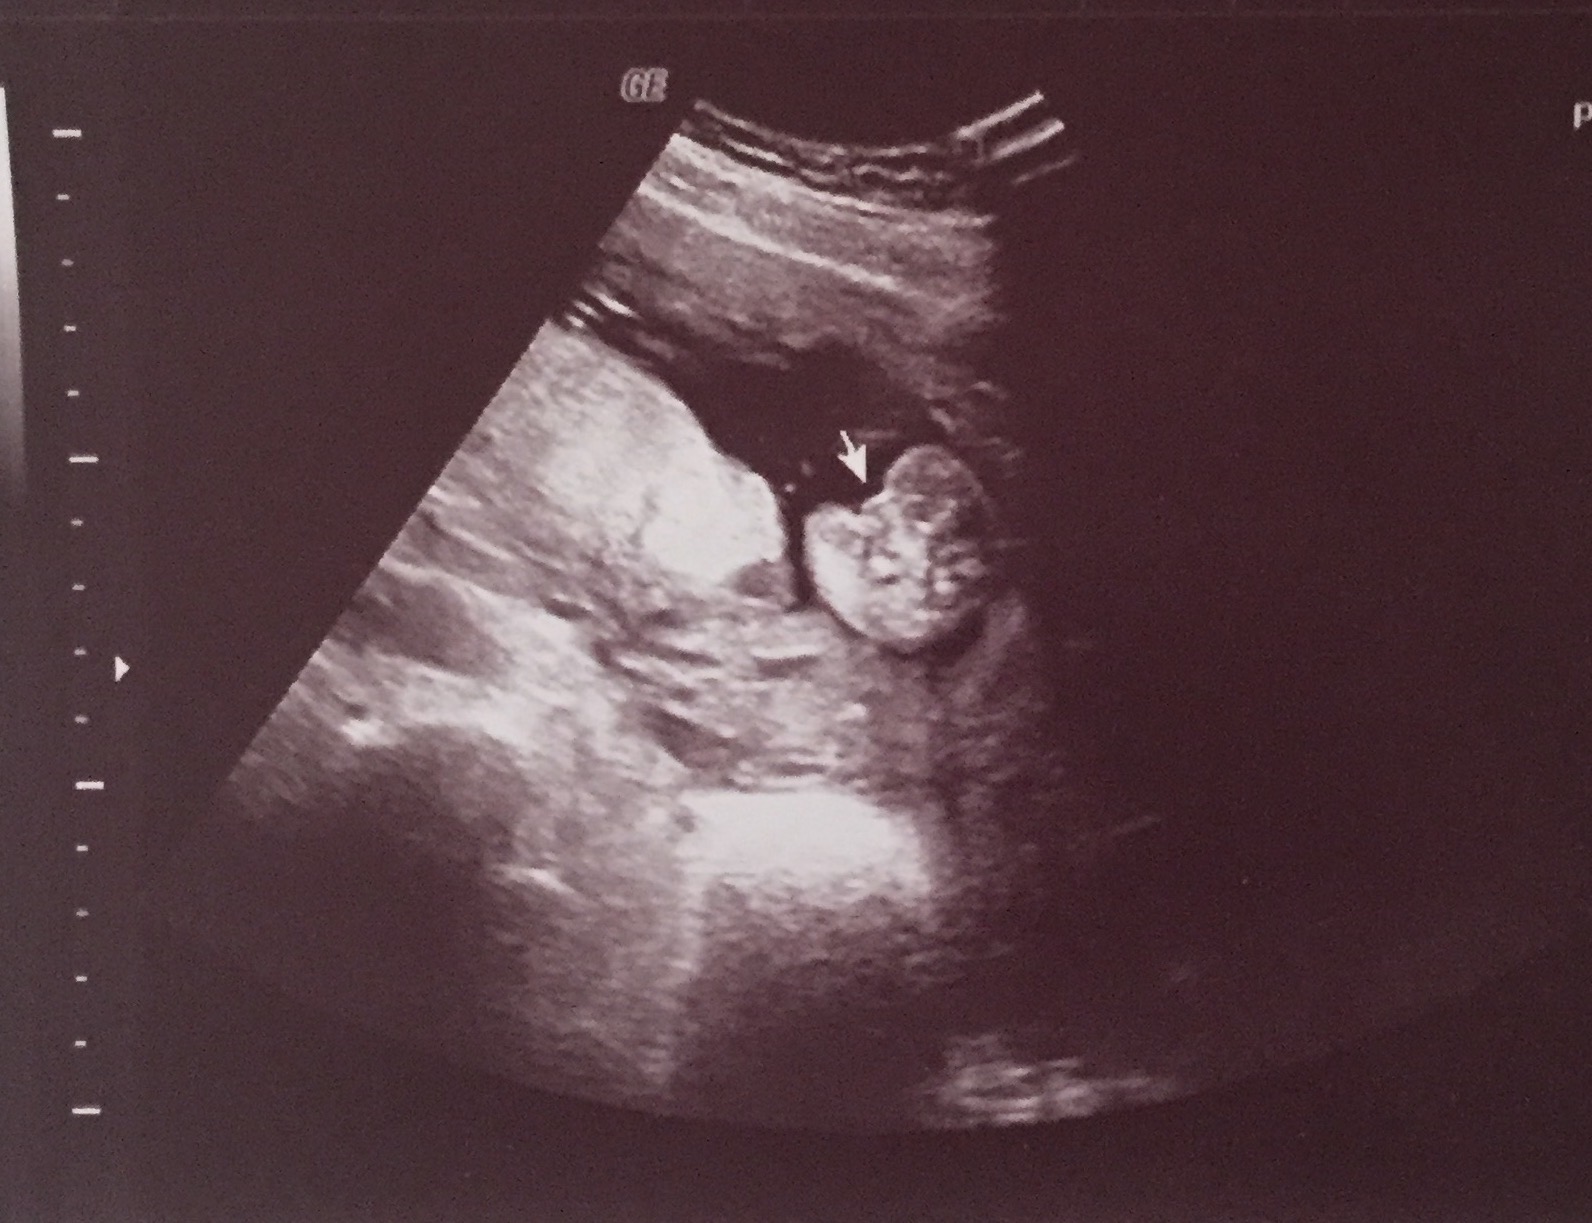

I had an elected 2d/4d ultrasound at 16 weeks and 3 days. The baby wasn't all that cooperative and the umbilical cord was between it's legs, blocking it's genitals. The baby lifted it's leg for a second and the ultrasound technician said that she saw the "hamburger buns" (labia). She continued trying to get the baby to open it's legs to get a clear shot and she said that she saw the three white lines of the vaginal bones multiple times and that she was confident it was a girl. She took a 2d picture of the supposed lines (picture below). However, she could not get a clear 3d shot because the baby would not open its legs to get a clear shot. I am curious to get others opinions on my ultrasound and if it looks like a girl or if it looks like it could be a boy because I don't want to tell everyone it's a girl and then be surprised at my 19 week scan when they tell me it's a boy.Attachment 35763Attachment 35764Attachment 35765Attachment 35766Attachment 35767